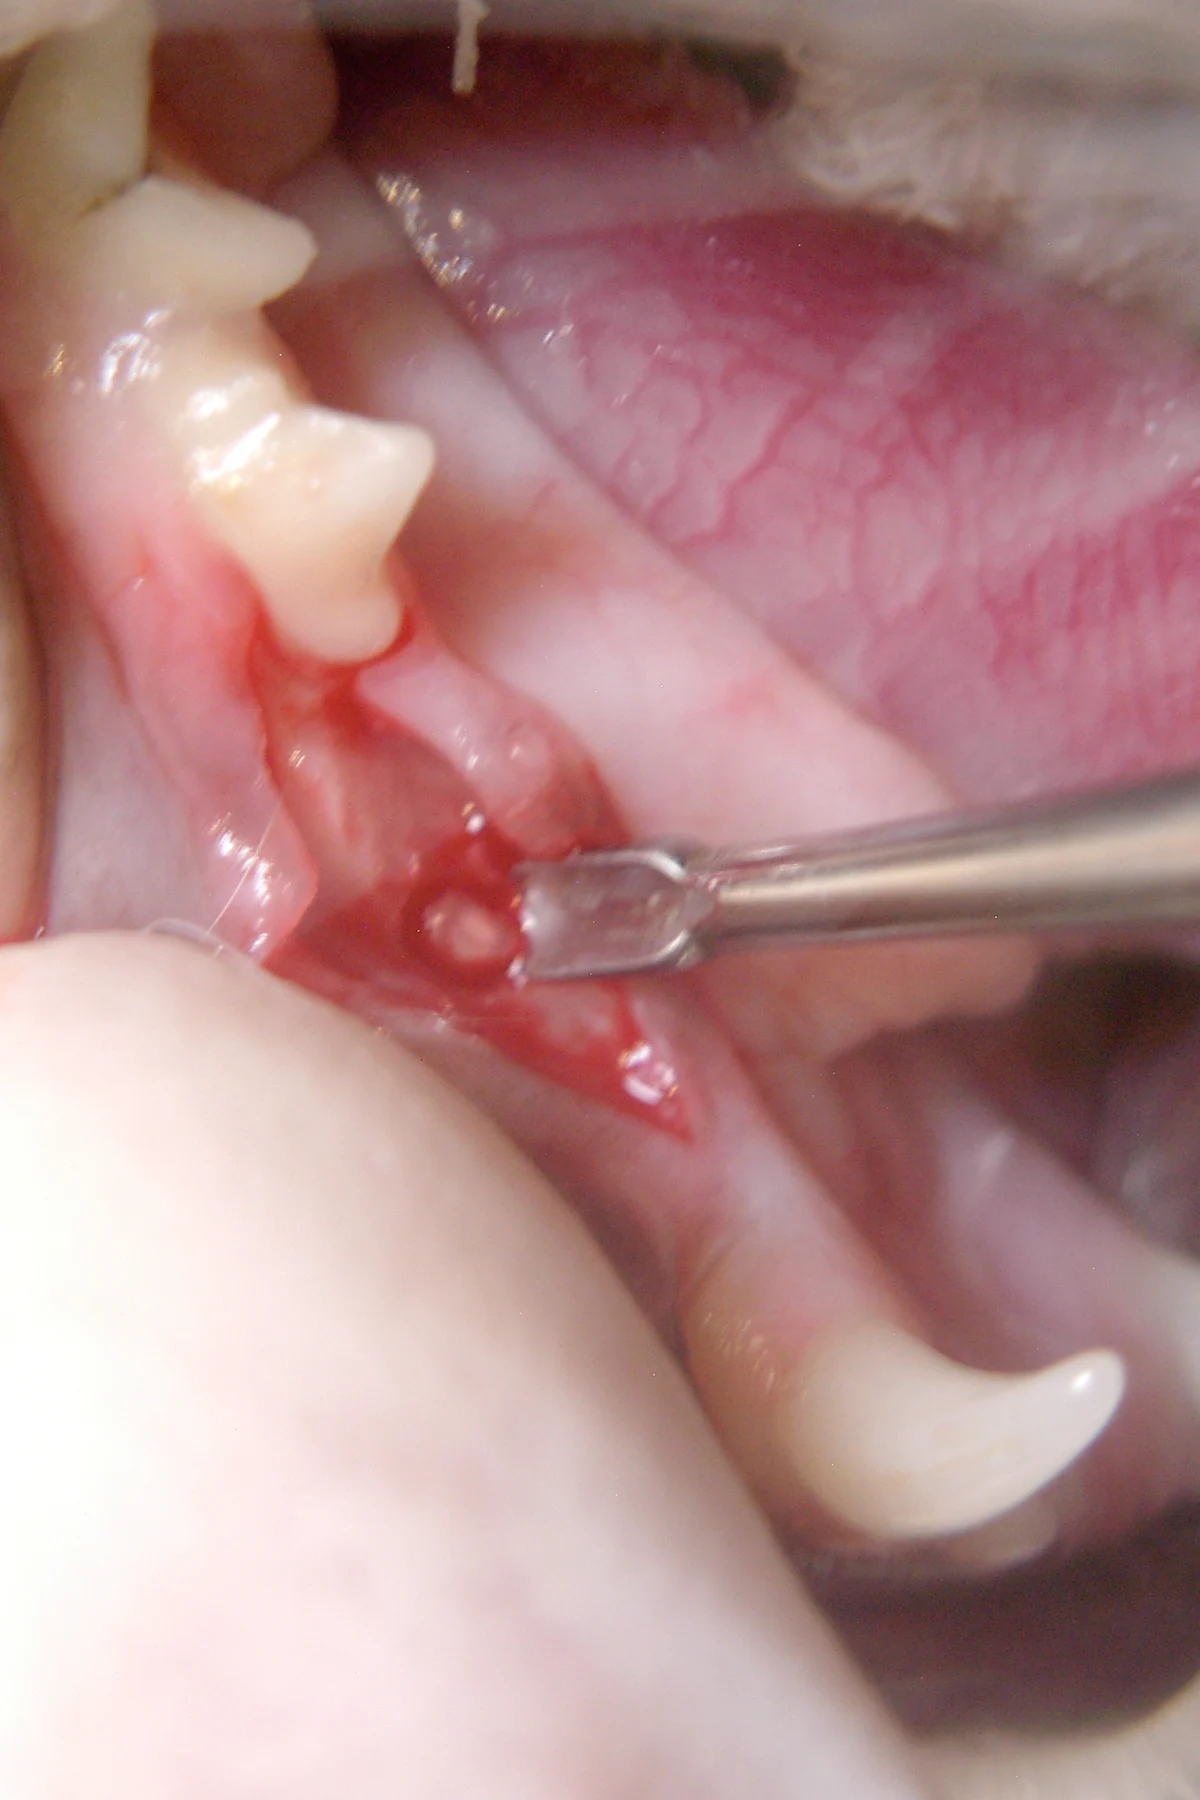

Step 6

A small (#1/4 round) burr is used to “outline” the periodontal ligament space of the mesial root, working circumferentially around the root structure 2 to 3 mm apically.4

Author Insight

Excavation around the retained mesial root allows for easy insertion of a dental elevator.